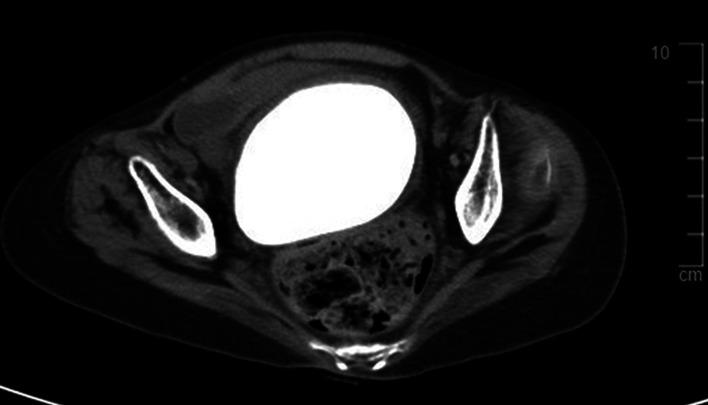

Primary vaginal stones have been rarely reported; the reports that do exist are usually case reports. Because of their low incidence, they are often misdiagnosed. This case report and literature review of a primary vaginal stone presents an assessment of symptoms and common risk factors for vaginal stone formation. A 28-year-old woman with spastic quadriplegia who had been bedridden for most of her life presented to the emergency department for abdominal distension and fever. She had chronic constipation, recurrent urinary tract infections (UTIs), and vaginal discharge. Abdominopelvic computed tomography (CT) was performed and a large stone observed. The vaginal stone was completely removed through the vaginal stump after hysterectomy. Differential diagnoses of vesicovaginal fistula, urethrovaginal fistula, genital anomaly, and ectopic ureter were made by performing several tests using indigo-carmine dye. She recovered from surgery without any complications. There was no recurrence of vaginal stones after 3 months. A biochemical analysis reported that the vaginal stone was 100% struvite. Vaginal stones are caused by repeated infections in an environment in which urine collects gradually. Patients with recurrent UTIs who are bedridden should be able to prevent vaginal stones with periodic gynecological examinations for early diagnosis and management.

原发性阴道结石鲜有报道;现有报道通常为病例报告。由于其发病率低,常被误诊。本病例报告及对原发性阴道结石的文献综述介绍了阴道结石形成的症状评估和常见危险因素。一名28岁患有痉挛性四肢瘫痪且一生大部分时间卧床的女性因腹胀和发热到急诊科就诊。她有慢性便秘、复发性尿路感染(UTIs)和阴道分泌物。进行了腹盆腔计算机断层扫描(CT),观察到一块大结石。子宫切除术后通过阴道残端将阴道结石完全取出。通过使用靛胭脂染料进行多项检查,对膀胱阴道瘘、尿道阴道瘘、生殖器异常和异位输尿管进行了鉴别诊断。她手术后康复,无任何并发症。3个月后阴道结石未复发。生化分析报告称,阴道结石100%为鸟粪石。阴道结石是由尿液逐渐积聚的环境中反复感染引起的。卧床的复发性UTIs患者应通过定期妇科检查进行早期诊断和管理,以预防阴道结石。